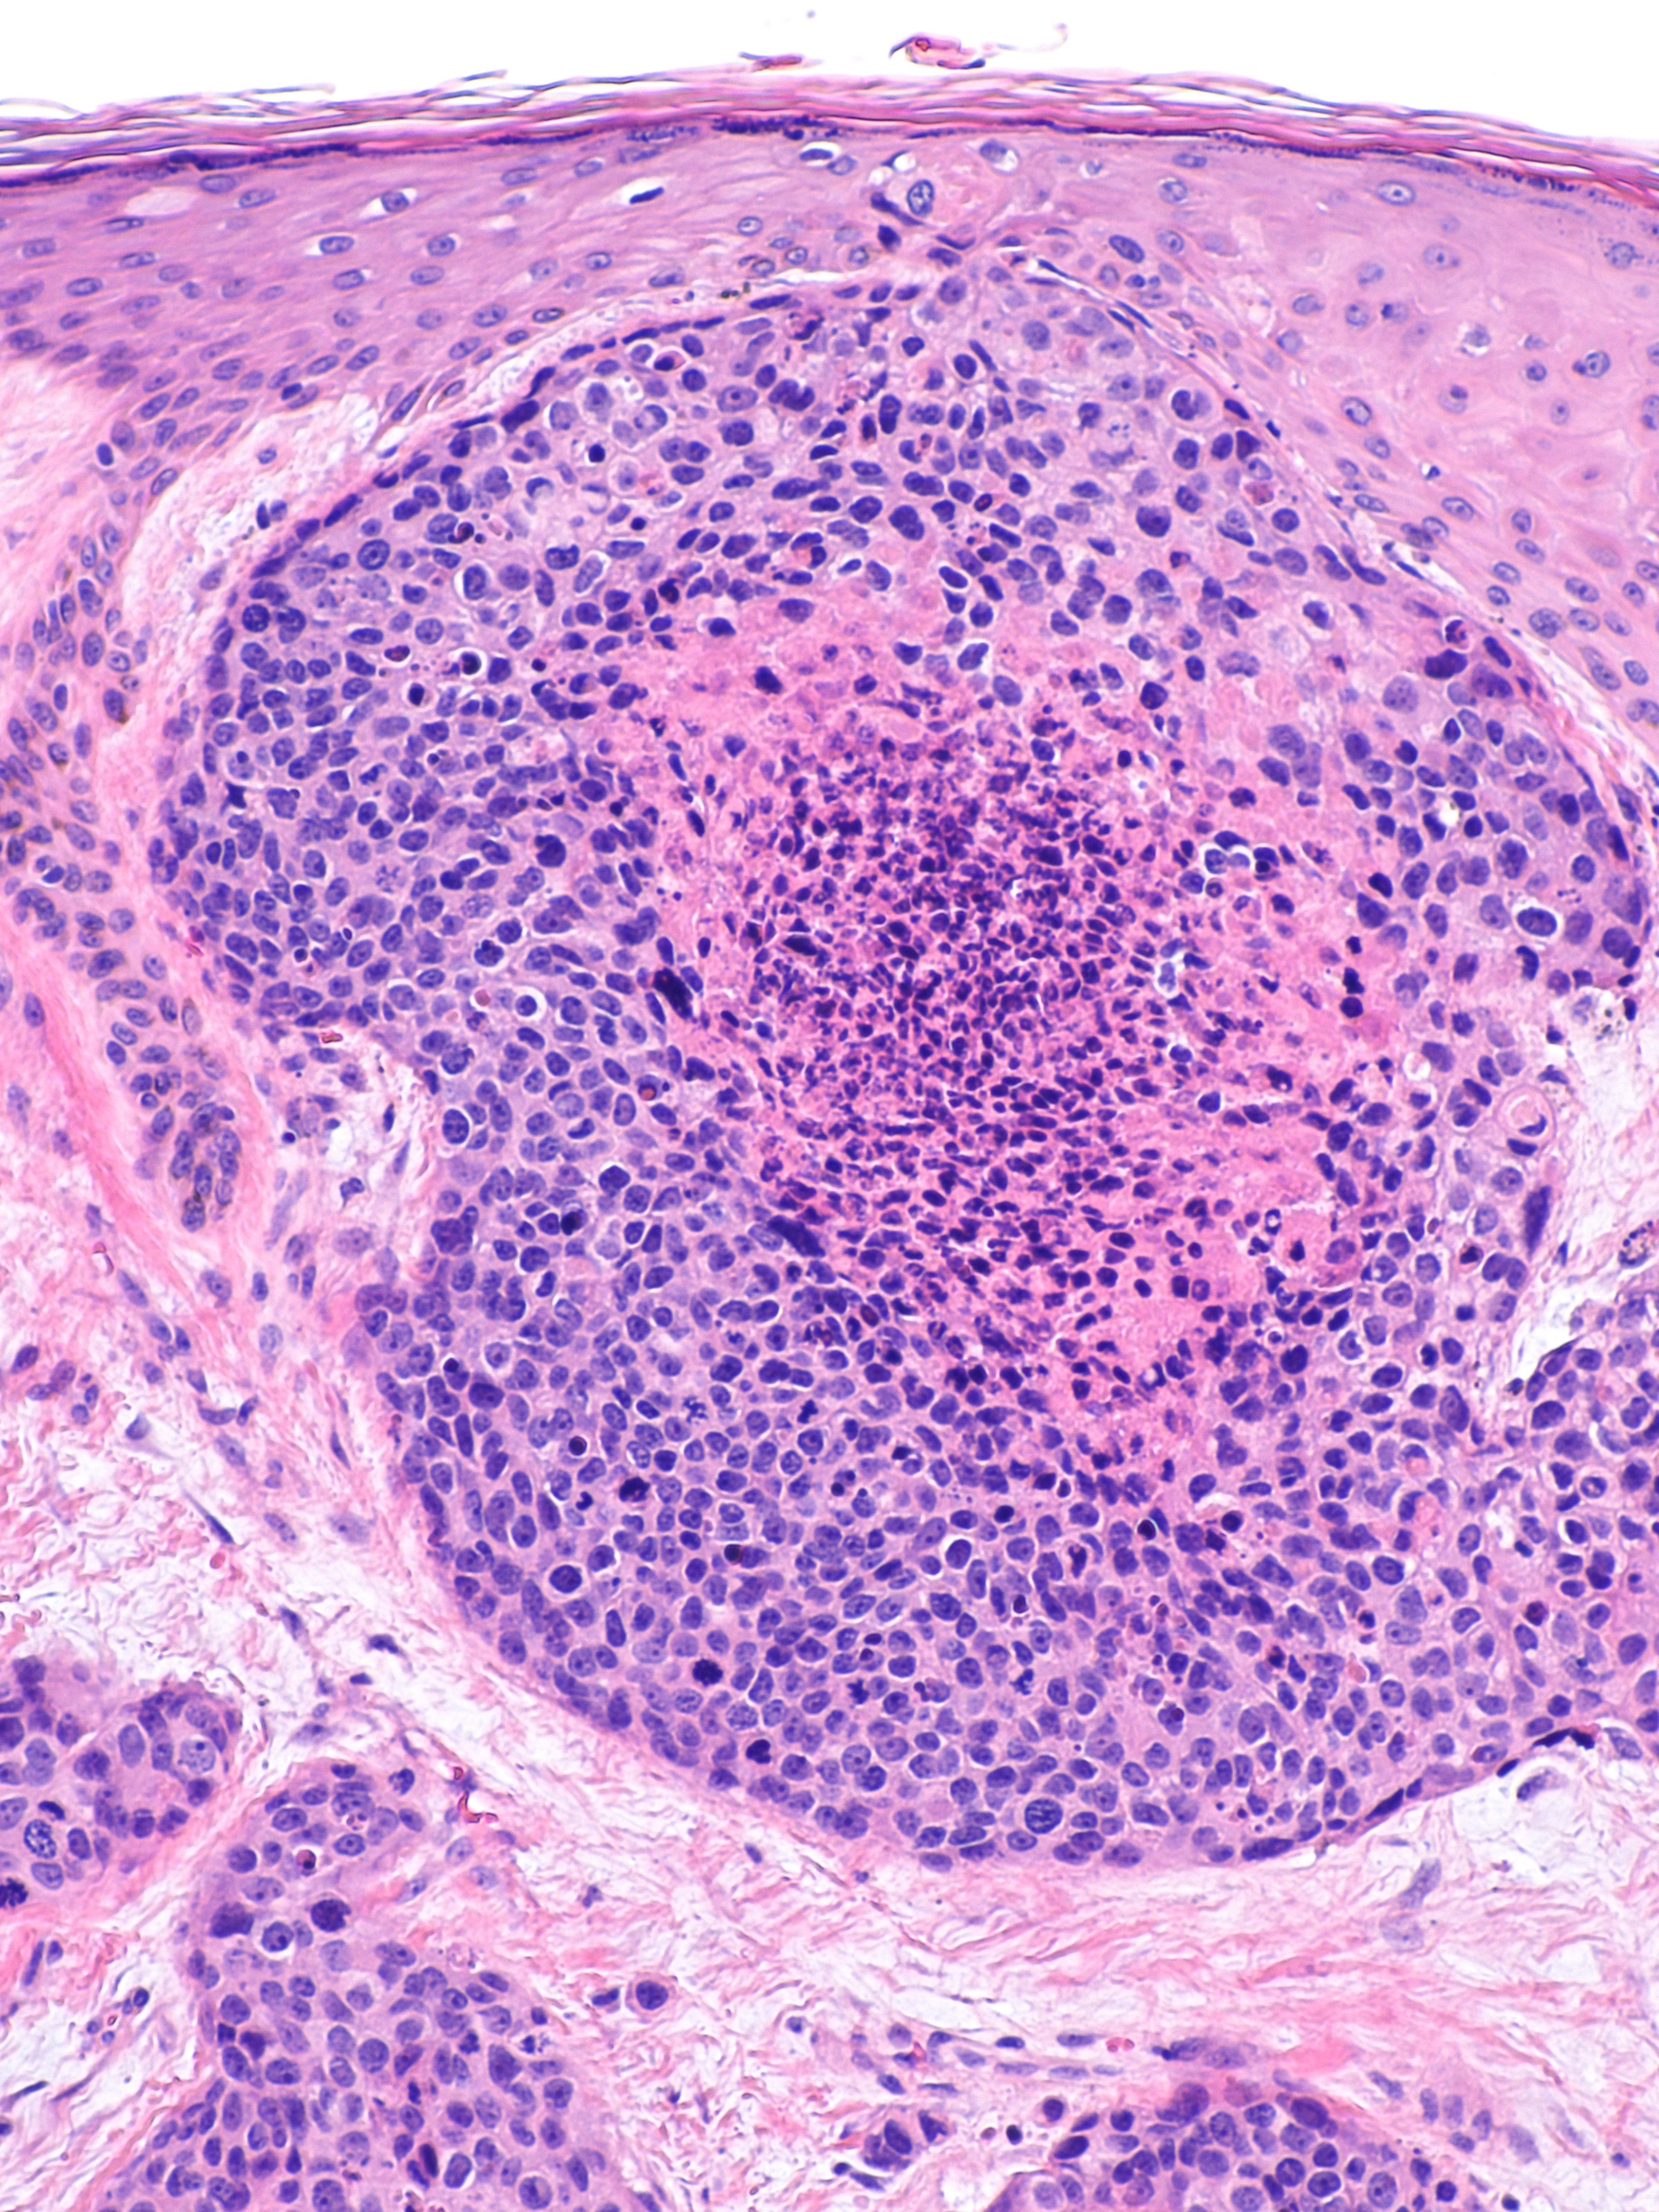

PA:

Multipele velden van basaloïde polygonale tumorcellen cellen met plaatselijk

ductale differentiatie, buis structuren met cuboïd epitheel. Uitgesproken cytologische

atypie, mitosefiguren. Soms ook squameuze differentiatie en dyskeratotische

cellen. Immunohistochemie: de ductale structuren kleuren aan met CEA (carcinoembryonic

antigen) en EMA (epithelial membrane antigen). De tumoren zijn meestal positief

voor CD117 (KIT), cytokeratin 19, c-KIT, en BerEP4. De prognose is slecht als

er invasie is van lymfbanen en vaten, meer dan 14 mitoses per high-power veld

en bij een tumordiepte > 7 mm.

| histologie

porocarcinoom |

histologie

PA-foto's: Michael Bonert (Nephron) - Wikimedia - Creative Commons License

3.0).